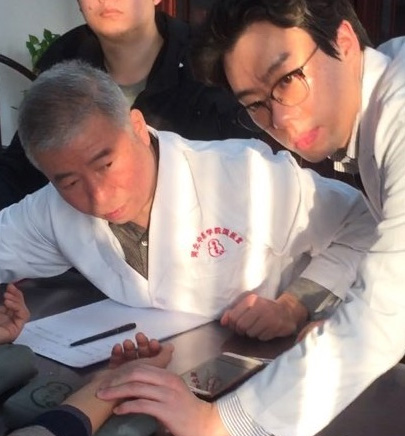

따라서 반복 재발되는 기흉 치료에 있어서 한의사의 경험과 실력은 매우 중요합니다.

북경과 상해의 호흡기 센터에 연수 다녀왔습니다.

난치병 치료의 대가로 손꼽이는 인물로 이사무(리스마오)선생이 있습니다.

중국 최고 의사 호칭인 국의대사(國醫大師)로 지정되었으며 현재는 수제자 왕사평 선생을 통해서 의술이 이어지고 있습니다.

그의 진료실에서 직접 사사받을 수 있는 기회를 가졌습니다.